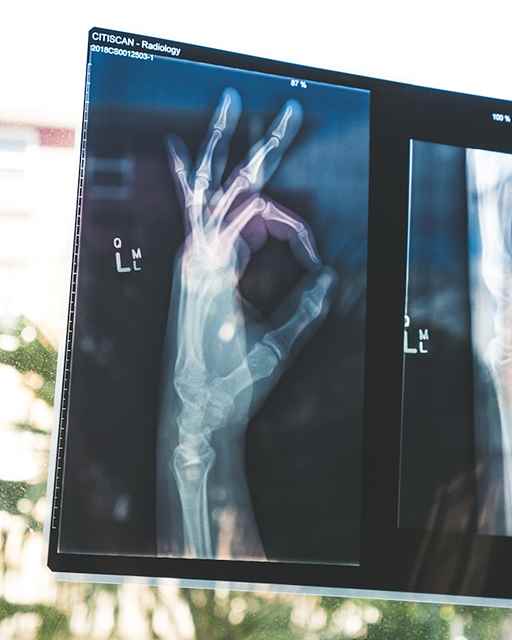

9. 악력 저하

손목이나 손의 골다공증과 관련된 골절은 악력과 손 기능의 저하로 이어질 수 있습니다. 항아리를 열거나 물건을 잡는 것과 같이 손재주가 필요한 작업을 수행하기 어려운 것은 근본적인 뼈 건강 문제를 나타낼 수 있습니다. 악력이나 손 기능의 저하를 발견했다면, 의사와 이러한 증상에 대해 논의하여 추가적인 평가와 개입이 필요한지 결정하는 것이 중요합니다.